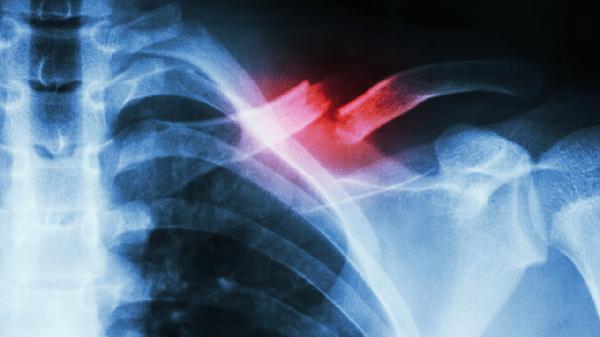

出現(xiàn)持續(xù)性鼻塞、面部脹痛需考慮治療。骨瘤阻塞竇口可能引發(fā)鼻竇炎,表現(xiàn)為膿性鼻涕、嗅覺減退,此時(shí)需通過鼻內(nèi)鏡評(píng)估竇口通暢度,合并感染時(shí)需先控制炎癥再?zèng)Q定是否手術(shù)。

年增長超過2毫米建議手術(shù)干預(yù)??焖偕L的骨瘤需排除骨化纖維瘤等病變,通過連續(xù)影像對(duì)比確認(rèn)生長速度,若壓迫鄰近眼眶或顱底結(jié)構(gòu),需耳鼻喉科聯(lián)合口腔頜面外科會(huì)診。

骨瘤導(dǎo)致竇腔引流障礙需手術(shù)切除。當(dāng)骨瘤占據(jù)上頜竇腔50%以上容積,或?qū)е吗ひ耗夷[形成時(shí),可采用鼻內(nèi)鏡下微創(chuàng)手術(shù),術(shù)中配合導(dǎo)航系統(tǒng)精準(zhǔn)切除。

反復(fù)鼻出血或神經(jīng)壓迫需積極處理。骨瘤表面黏膜潰瘍可能引發(fā)出血,壓迫眶下神經(jīng)會(huì)導(dǎo)致面部麻木,這類情況建議選擇低溫等離子刀或動(dòng)力系統(tǒng)切除。